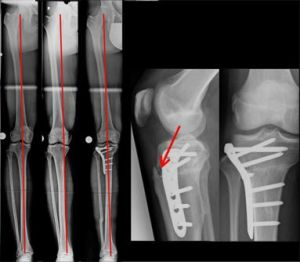

Um alle Aspekte in einer Osteotomie zu korrigieren, wurde eine horizontale Osteotomie „hinter“ dem Kniescheibensehnenansatz (roter Pfeil) gewählt, welcher bei der Drehkorrektur mit nach innen gedreht wurde.

Bild 15, links: Fuß „normal“ noch vorne, Kniescheibe (= Knie) dann zu weit innengedreht.

Bild 15, 2. Abb. von links: Knie „normal“ nach vorne ausgerichtet, was zu einer Verstärkung der O-Beinfehlstellung führt.